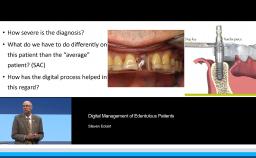

Part one of a two-part presentation gives a comprehensive overview of how to treat complex cases using an interdisciplinary approach in implant dentistry. From the prosthodontist’s point of view, the workflow starts with careful prosthetic planning by the use of wax-ups or set-ups, and in some cases orthodontic pretreatment is indicated. This lecture demonstrates how the prosthetic planning is then transferred by surgical templates to facilitate the correct 3D prosthodontically driven implant placement. In this workflow, the provisional prosthesis conditions the soft tissue in order to optimize esthetics prior to finalizing the prosthetic rehabilitation. This lecture includes a series of ‘Prosthetic Rules’ to serve as benchmarks for effective prosthodontically driven treatment.

- discuss the need for a multidisciplinary approach integrating prosthetic and surgical issues in implant dentistry

- describe the workflow of careful prosthetic planning, surgical templates during implant placement, provisional prosthesis with soft tissue conditioning, and final rehabilitation